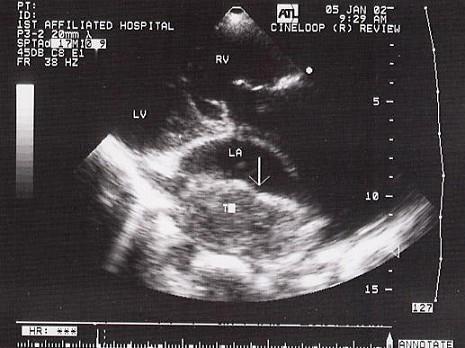

该病例最可能的诊断?(?)A.黏液瘤B.心房血栓C.心房云雾影D.房壁增厚E.赘生物

问题 该病例最可能的诊断?(?)

选项 A.黏液瘤 B.心房血栓 C.心房云雾影 D.房壁增厚 E.赘生物

答案 B